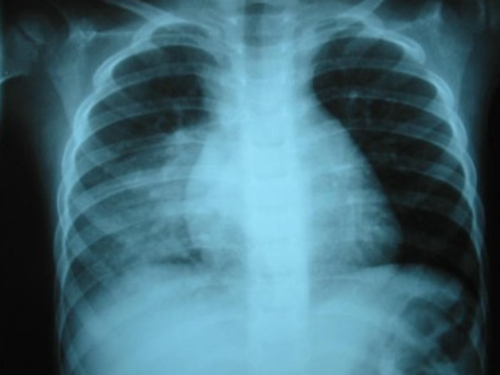

Los síntomas iniciales de la pulmonía son tos persistente y dificultad para respirar.